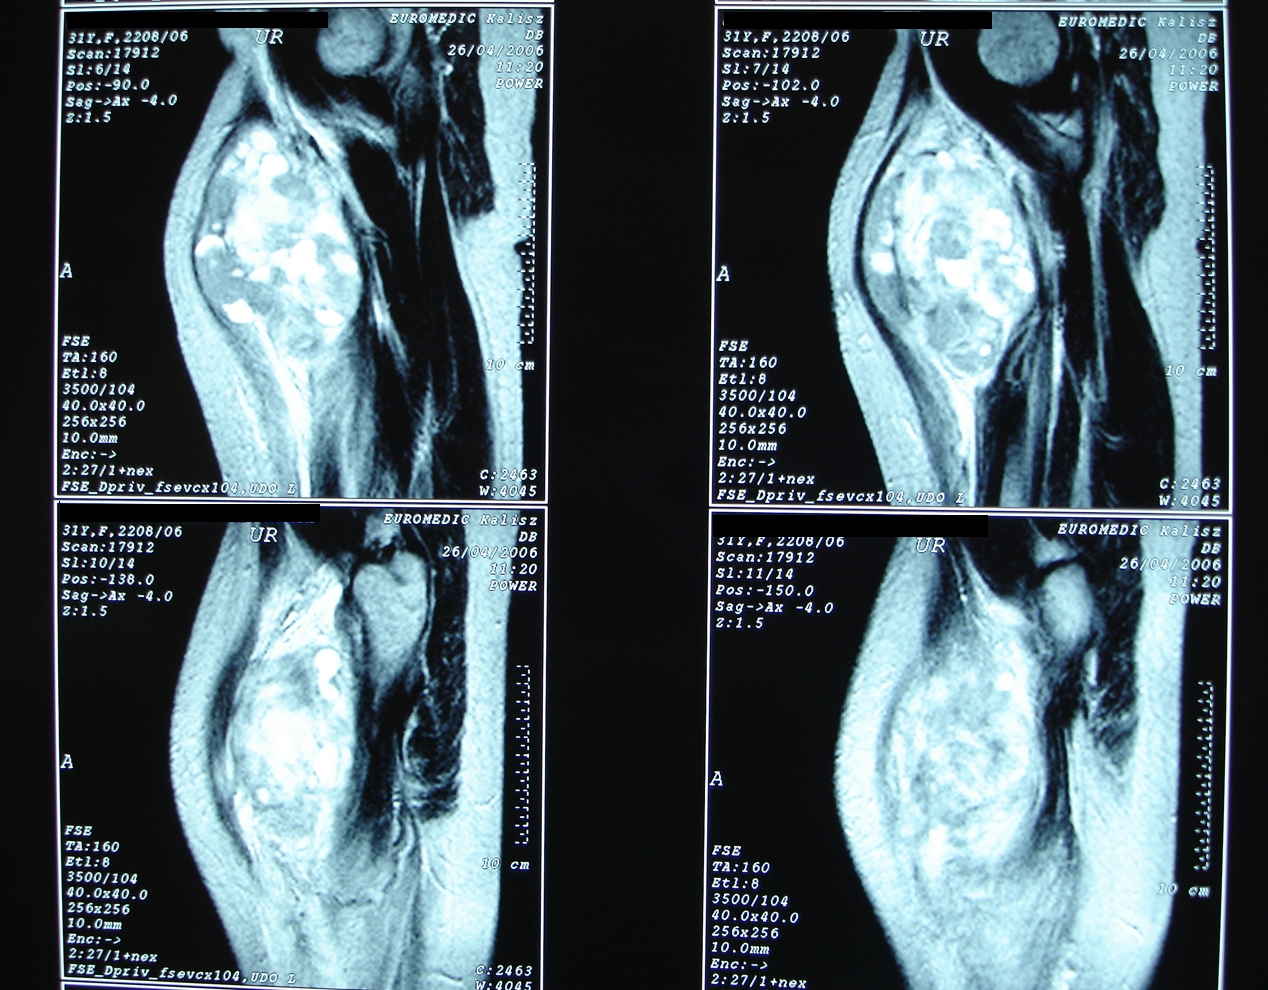

Przekrój podłużny uda - widoczna olbrzymia masa guza

Przekrój podłużny uda - widoczna olbrzymia masa guza